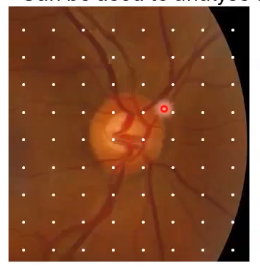

can be used to analyse disc topography and surrounding RNFL thickness

measurements of rim/disc area, C/D ratio, cup volume

(1) /; otpic disc cube; onh topography analysis

defines a point, anythign deeper is cup anything above is rim

for analysis the cup is anything below the reference line

reference line is set 150 micrometeres above the adjacent retinal pigment epithelium- this is completely arbitary, not a reason why it is placed at that point